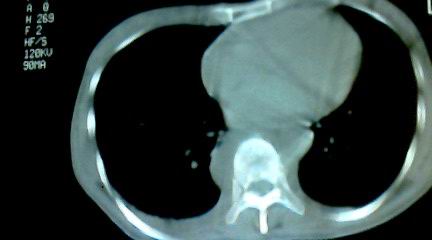

标题: CT25218:请教!胸部CT,胸8椎体骨质破坏,伴周围软组织肿。 [打印本页]

标题: CT25218:请教!胸部CT,胸8椎体骨质破坏,伴周围软组织肿。

患者,女41岁,肢体乏力。

两肺上叶继发性肺结核;胸椎结核并椎旁寒性脓肿形成。

胸椎结核并椎旁寒性脓肿形成。

支持两肺上叶继发性肺结核;胸椎结核并椎旁寒性脓肿形成

两肺上叶继发性肺结核;胸椎结核并椎旁寒性脓肿形成